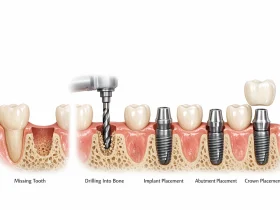

به طور کلی فرآیند ایمپلنت شامل مراحل زیر است:

- بررسی و برنامهریزی درمان

- جراحی قرار دادن پایه ایمپلنت

- دوره ترمیم و جوش خوردن ایمپلنت با استخوان

- نصب اباتمنت

- قرار دادن روکش دندان

کل این فرآیند معمولاً بین ۳ تا ۶ ماه زمان نیاز دارد، زیرا بدن باید فرصت کافی برای ترمیم بافتها و اتصال ایمپلنت به استخوان فک داشته باشد.